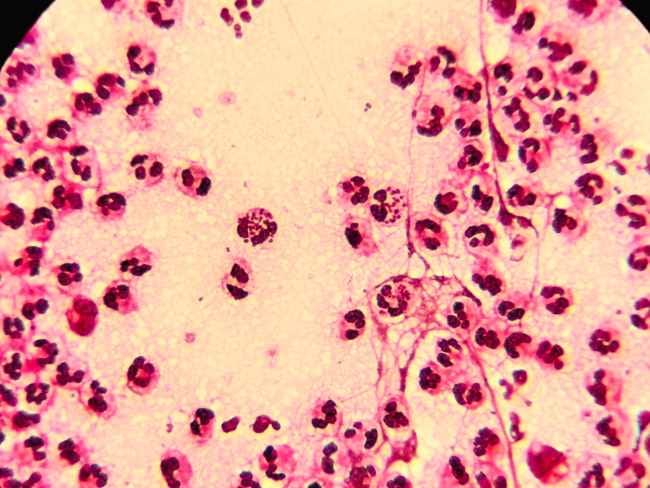

Neisseria gonorrhoeae merupakan bakteri yang berbentuk seperti kacang merah. Bakteri ini dapat hidup di tempat yang hangat dan lembap pada tubuh manusia, misalnya mata, tenggorokan, rektum, uretra, dan saluran reproduksi wanita, seperti leher rahim, rahim, dan tuba falopi.